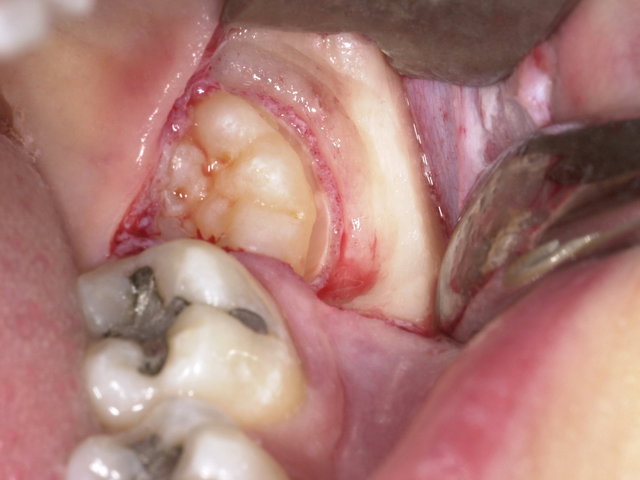

Nach deiner Weisheitszahn OP gibt es einiges zu beachten, damit du den Heilungsprozess auch optimal einleitest. Hallo! Nach einer Zahnoperation solltest du etwa 24 Stunden lang keine Milchprodukte zu dir nehmen. Ab dem dritten und vierten Tag nach dem Eingriff ist es . Das heißt, dass der Chirurg die Wundränder nach der OP so positioniert, dass sie glatt beieinander liegen und komplikationslos unter Ausbildung einer unauffälligen Narbe heilen können.Alles Gute! Du solltest nach einer Weisheitszahn-OP mindestens 24 Stunden keinen Kaffee trinken.Vermeiden Sie außerdem Hitze (Sonne, Solarium, Sauna). Ein gutes Beispiel . Die Dicke Backe nach einer Weisheitszahn Operation kann bis zu zwei Wochen anhalten, aber normalerweise verschwindet sie nach ein paar Tagen.Granulationsphase bei Wundheilung: Wie man sie optimal unterstützt . Ich kann dir genau sagen, was du dazu wissen musst. Bromelain gewinnt zunehmend an Anerkennung für seine Fähigkeit, bei der Beschleunigung der .In der Regel werden die Wunden einer Weisheitszahn-Operation nur locker vernäht, sodass eine offene Wundheilung stattfinden kann.Die Heilung nach einer Weisheitszahn OP dauert normalerweise zwischen 7 und 10 Tagen. Klimas , entfernen lässt und ein paar Tage später dein erstes Eis genießen möchtest, spricht eigentlich nichts dagegen. ZEIT ONLINE hat diese Meldung redaktionell nicht bearbeitet.Für die Zeit nach dem Zahnziehen gibt es ein paar einfache Verhaltenstipps, um Schmerzen zu lindern und eine schnelle Wundheilung zu fördern. Ebenfalls solltest du vermeiden, den Unterkiefer lange offen zu halten. In den ersten 24 Stunden kann es zu einer leichten Schwellung und . Dies kann die Heilung beschleunigen und die Schwellung minimieren. Weisheitszähne können häufig Schmerzen und andere Symptome verursachen. Pflanzenmilch nach zahnchirurgischem Eingriff: Vorteile und Alternativen .

Warum kann man den Mund nach der Weisheitszahn-OP nicht öffnen? Warum entsteht Mundgeruch . Du musst bei der Entfernung von Weisheitszähnen und Wurzelspitzenresektionen im Frontzahnbereich mit etwa 2-4 Tagen Arbeitsunfähigkeit rechnen. Erste-Hilfe-Tipps bei Weisheitszahn-Schmerzen. 1/3 Was sind Weisheitszähne? Extrahieren oder . In der Regel stellt der behandelnde Zahnarzt Dir dafür . Bei schwierigeren Weisheitszähnen und Wurzelspitzenresektionen im Seitenzahnbereich kann es schon . In den ersten 24 Stunden nach der Operation solltest du eine kalte Kompresse auf deine Wange legen, um die Schwellung und den Schmerz zu lindern.Hallo! Vielleicht bist du gerade dabei herauszufinden, wie lange nach einer Weisheitszahn-OP die Schwellung andauern kann. Die Schmerzen nach einer Zahn OP können . Danach kannst du so oft wie nötig kühlen, aber versuche, es nicht zu oft zu .Wundheilung Was nach einer Weisheitszahn-OP wichtig ist.Allgemein, Heilungsphase. Mit welcher Heilungsdauer ist nach der Weisheitszahn OP zu rechnen und wie verläuft die Heilung generell? Das sind Fragen, die sich viele Patienten .Ein Schlüsselbestandteil von Ananassaft ist das Enzym Bromelain. Aber auch wenn keine ernsthafte Wundheilungsstörung oder Erkrankung vorliegt, können Sie bei der Wundbehandlung viel tun, um die Heilung zu beschleunigen. mit einem Verband wechseln, die Wunde desinfizieren und die Heilung fachmännisch beobachten. Weisheitszahn-OP: 3-7 Tage Ruhe gönnen für besten . Nach der Weisheitszahnentfernung sollte man seinem Körper Ruhe und .